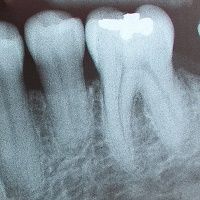

State regulations only allow MassHealth to pay for periapical radiographs once every three years as part of a full-mouth series. MassHealth will also pay when the procedure is necessary for specific areas when a dentist anticipates extraction or suspects an infection.

However, the auditor’s report said that Tahoun’s practices ordered and billed MassHealth for these radiographs as part of routine dental exams without a full-mouth series or documentation of pain, infections, or other issues.